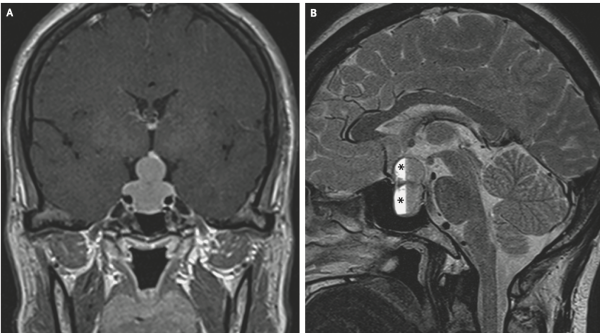

Женщина, 47 лет, с жалобами на прогрессирующую головную боль, нечеткое зрение, галакторею и нарушения менструального цикла в течение последнего месяца. Острота зрения пациентки при осмотре составила около 0,4 (20/50 в американской системе), офтальмологической патологии не обнаружено. С помощью МРТ выявлено увеличение гипофиза с интрасупраселлярным ростом и сдавлением хиазмы (перекреста зрительных нервов). Также наблюдалось внутригипофизарное кровоизлияние.

На МРТ наблюдался «знак снеговика», возникающий при опухолях, медленно растущих вверх из турецкого седла. Лабораторные исследования подтвердили повышенный уровень пролактина в сыворотке крови (более 200 мг/мл), а также центральную надпочечниковую недостаточность и центральный гипотиреоз.